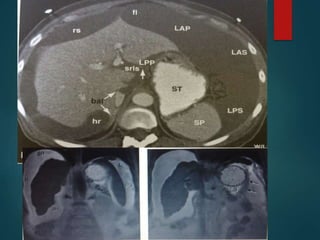

Sclerosing Mesenteritis…

• Multiple synonyms having wide histological

spectrum: mesenteric panniculitis, retractile

mesenteritis and mesenteric lipodystrophy.

• Pathologically it is a chronic inflammation of

unknown etiology.

• The signs and symptoms are variable.

Patients present with pain, a palpable mass or

bowel complications, but in many cases it is an

incidental finding on CT made for other reasons.

Sclerosing

Mesenteritis

(panniculitis).

Sclerosing Mesenteritis… • Multiplesynonyms having wide histological spectrum: mesenteric panniculitis, retractile mesenteritis and mesenteric lipodystrophy. • Pathologically it is a chronic inflammation of unknown etiology. • The signs and symptoms are variable. Patients present with pain, a palpable mass or bowel complications, but in many cases it is an incidental finding on CT made for other reasons.

• #44 Coronal (A), sagittal (B) and transaxial (C) volume-rendered computed tomography shows diffusely increased attenuation of the central small bowel mesenteric fat. Note the enlarged mesenteric lymph nodes (arrows).